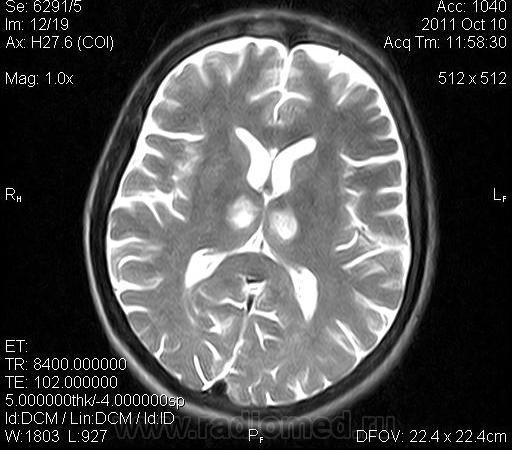

женщина 1963 года рождения. давность заболевания 10 дней.

ОНМК в бассейне правой и левой СМА (центральные ветви), подострый период.. Билатеральность нарушений может быть обусловлена вариантом строения Виллизиева круга.

Билатеральный таламический инфаркт. Либо венозный, либо вследствие закупорки одной из ветвей задней мозговой артерии - ЗМА (вариан развития ЗМА). Но не средней мозговой артерии (СМА). Мне представляеться, что здесь второе... За венозный инфаркт данных не вижу.

Я неприклонен... Инфаркт ЗМА (вероятно, варианта развития левой ЗМА - эмболии, мойа-мойа..).